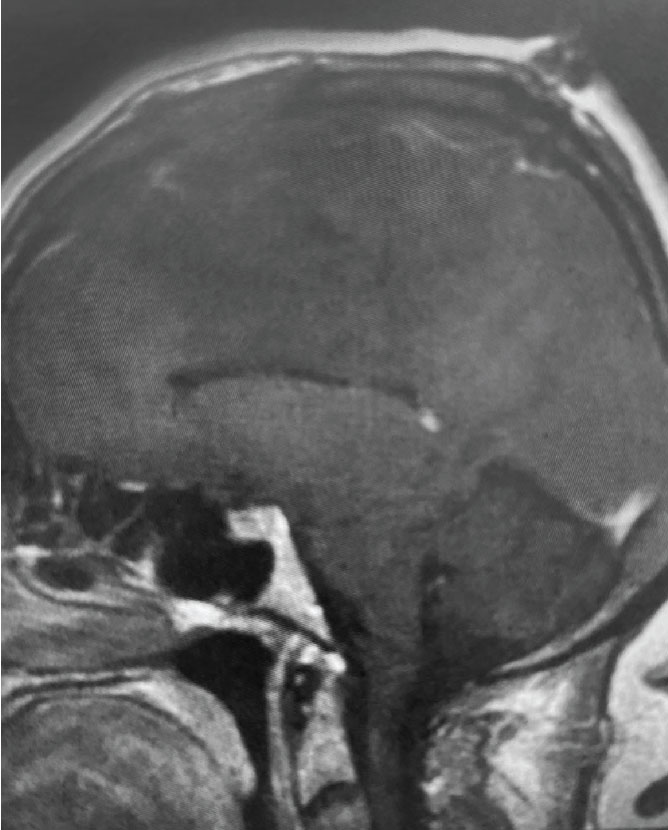

B) Pre-operative, sagittal post-contrast MRI

Fig 1. B) Pre-operative, sagittal post-contrast MRI.

A) Post-operative, post-contrast, sagittal MRI

Fig 2. A) Post-operative, post-contrast, sagittal MRI.